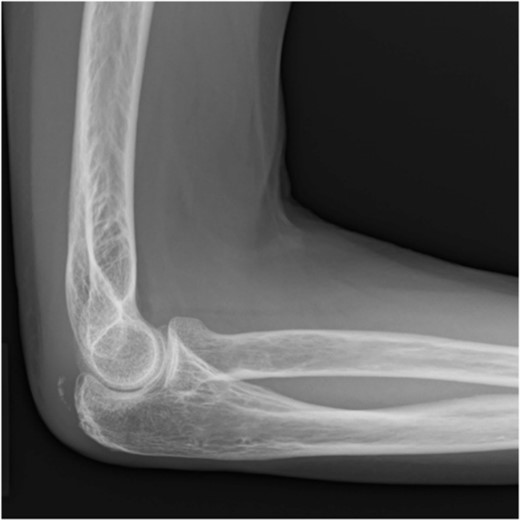

Postoperative radiography revealed reduced bone fragmentation (Fig. 5). The elbow was immobilized at 90° for 1 week postoperatively; range-of-motion exercises were started in postoperative week 2. Radiographs obtained 4 months postoperatively showed bone union (Fig. 6). At 18 months postoperatively, the patient had a range of motion of 140° flexion and 0° extension. The disability of the arm, shoulder and hand score was 0.

Postoperative lateral elbow radiographs. The bone fragment is reduced and fixed.